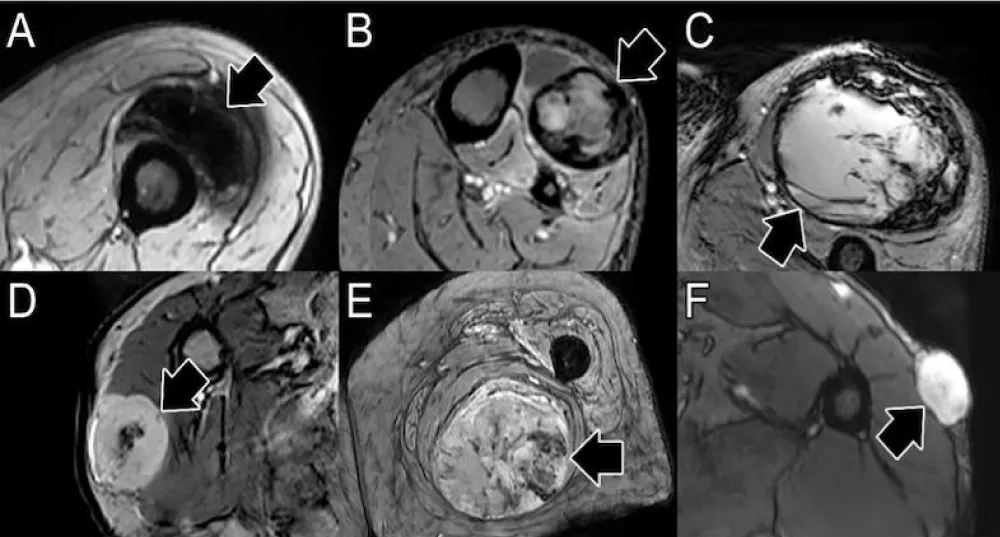

CE-SWI

Susceptibility-weighted imaging (SWI) is a 3D high-spatial-resolution, velocity-corrected gradient-echo MRI sequence. It creates images with magnitude and filtered-phase information and uses tissue magnetic susceptibility differences to generate signal contrast [12]. The signal arises from paramagnetic (hemosiderin), diamagnetic (minerals and calcifications), and ferromagnetic (metal) molecules, resulting in a loss of signal that can be analyzed for patterns [12,27]. Our findings displayed that responders present a CE-SWI Complete Ring pattern at PS, while partial/non-responders mainly demonstrate Incomplete Ring and Globular patterns. Representative RMS patients presenting these patterns of response are shown in Figure 9. A pre-surgical complete ring pattern has also been reported as a biomarker of response in previous studies, including those of patients with UPS and LMS [19,28]. These CE-SWI patterns are most commonly observed at the endpoint of therapy, when treatment-induced necrosis, fibrosis, and hemorrhage have led to the formation of a ring-like fibrous and hemosiderin-rich tumor capsule, characterized by distinct and profound T2* peripheral hypointensity [19]. The present study and previous publications regarding UPS, LMS, and desmoid tumors highlight the utility of CE-SWI in assessing soft tissue tumors [19,28,29].

Download Image

Figure 9: CE-SWI patterns observed pre-surgically and their correlation with PATE. A. Complete ring with 90% PATE. B. Incomplete ring with 70% PATE. C. Globular pattern with 30% PATE. PATE: pathology-assessed treatment effect.